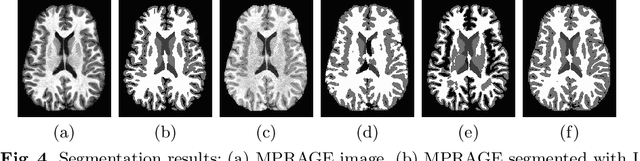

Abstract:Deep learning approaches to the segmentation of magnetic resonance images have shown significant promise in automating the quantitative analysis of brain images. However, a continuing challenge has been its sensitivity to the variability of acquisition protocols. Attempting to segment images that have different contrast properties from those within the training data generally leads to significantly reduced performance. Furthermore, heterogeneous data sets cannot be easily evaluated because the quantitative variation due to acquisition differences often dwarfs the variation due to the biological differences that one seeks to measure. In this work, we describe an approach using alternating segmentation and synthesis steps that adapts the contrast properties of the training data to the input image. This allows input images that do not resemble the training data to be more consistently segmented. A notable advantage of this approach is that only a single example of the acquisition protocol is required to adapt to its contrast properties. We demonstrate the efficacy of our approaching using brain images from a set of human subjects scanned with two different T1-weighted volumetric protocols.